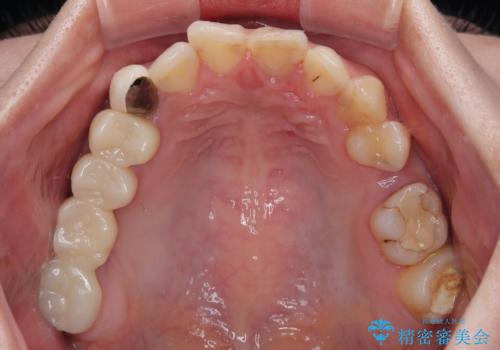

- むし歯により神経を取り除く処置をした歯と隣接する歯の捻れを気にして来院された患者様です。

神経を取り除いた歯は変色が始まっており、隣の歯は捻れにより突出している印象であったので、前歯2歯をオールセラミッククラウンにて補綴することとしました。

捻れている歯は、神経が露出する可能性があり、その場合には根管治療が必要となります。